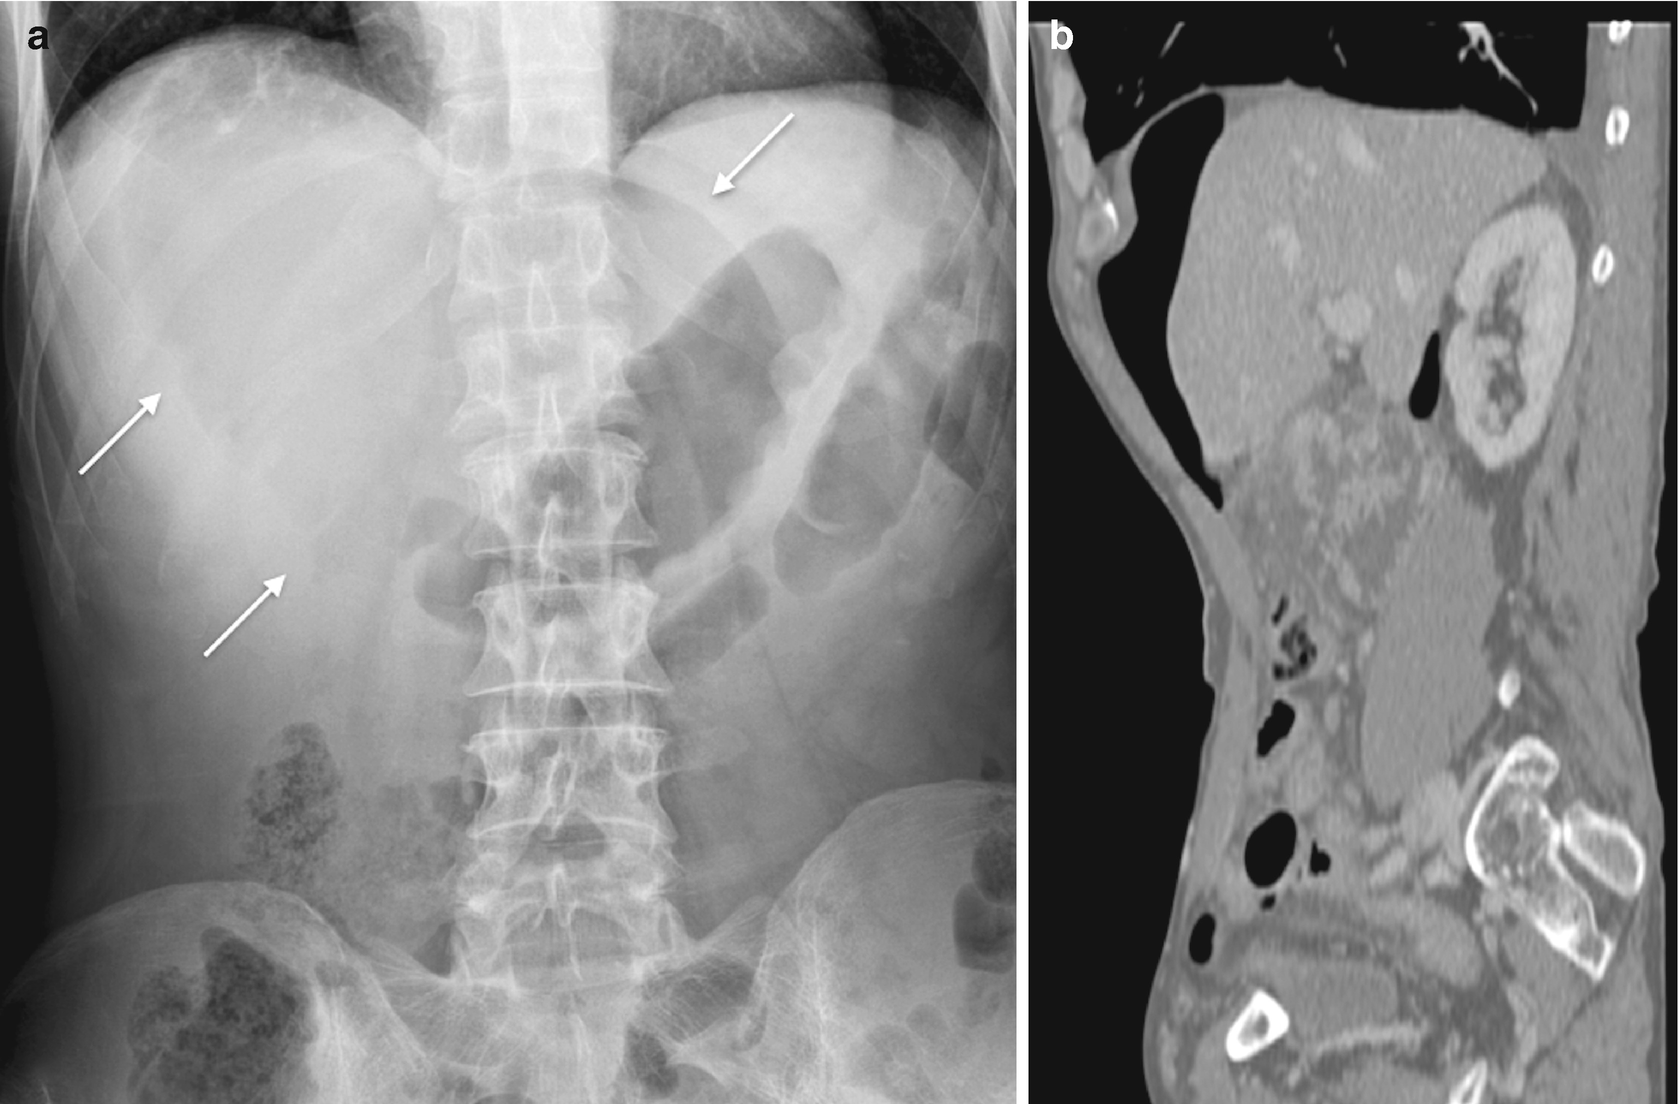

Analysis of roentgen signs in general radiology v 3 pdf. Sign in to set up alerts. 16 chapman s nakielny r. The roentgen signs of diffuse alveolar involvement differ considerably from those seen with other sites of disseminated pulmonary involvement. This alveolar pattern can usually be identified.

Detected early these signs can often be used to predict the causative agent and pathophysiologic mechanism and possibly to optimize patient care. For example a number of biomarkers are frequently used to determine risk of lung cancerfirst a simple lesion in the lung detected by x ray ct or mri can lead to the suspicion of a neoplasm. One microroentgen abbreviated ur is one millionth of a roentgen. It is abbreviated with the capital r.